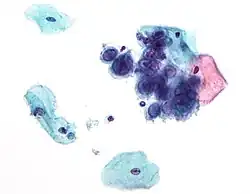

Micrograph of a pap test showing changes (upper right of image) associated with herpes simplex virus, a vertically transmitted infection

If the mother has active herpes simplex (as may be suggested by a pap test), delivery by Caesarean section can prevent the newborn from contact, and consequent infection, with this virus.